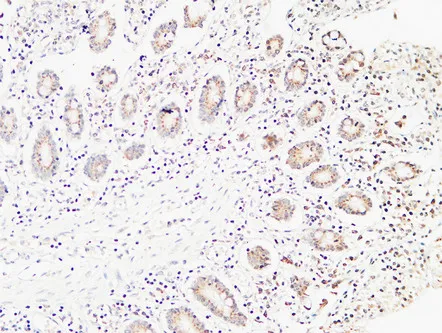

Endoglin Rabbit Polyclonal Antibody

Cat: APRab10463